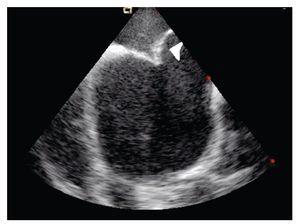

The transeptal puncture was performed under direct ultrasound guidance (Figure 1). After hemodynamic confirmation of left atrial curve morphology, the Mullins catheter was advanced and exchanged for a spiral guide-wire. Interatrial septum was dilated with the usual technique and an Inoue 28 balloon was advanced through the mitral valve into the left ventricle under direct ultrasound guidance (Figure 2). Mitral valvuloplasty at the level of the valve (Figure 3) was performed by a single inflation with the Inoue balloon with 28 ml of normal saline. ICE analysis across the mitral valve showed a significant drop of mean transmitral valve gradient and an increase of the mitral valve area, without an increase of mitral regurgitation.

Figure 3. Shows the Inoue balloon inflated (arrow) with a waist in its middle; mitral valvular plane in long-axis view.